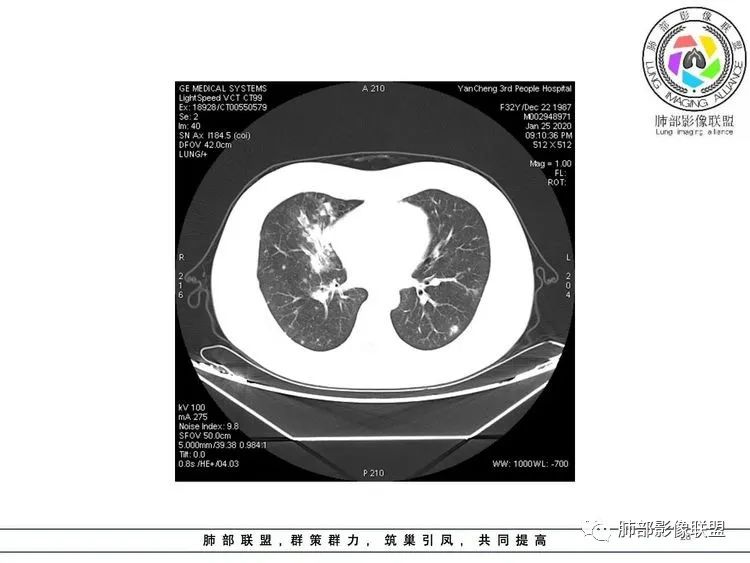

这些层面存在支气管壁增厚,或者伴有支气管周围炎症,属于气道播散

右下肺,小圆圈的是支气管壁增厚,大圆是支气管周围实变,也是气道播散 医学百科网 | YxBaike.Com

这些病灶应该是先出来的,然后形成病毒血症后再出现两肺血管周围的结节, 医学百科网 | YxBaike.Com

@吴明忠 浙江嘉善二院放射科 我是这样猜测的,先支气管炎、支气管肺炎,后形成病毒血症,出现血道结节,供参考。

5.复查存留高密度结节影应当符合肉芽肿结节。 医学百科网 | YxBaike.Com